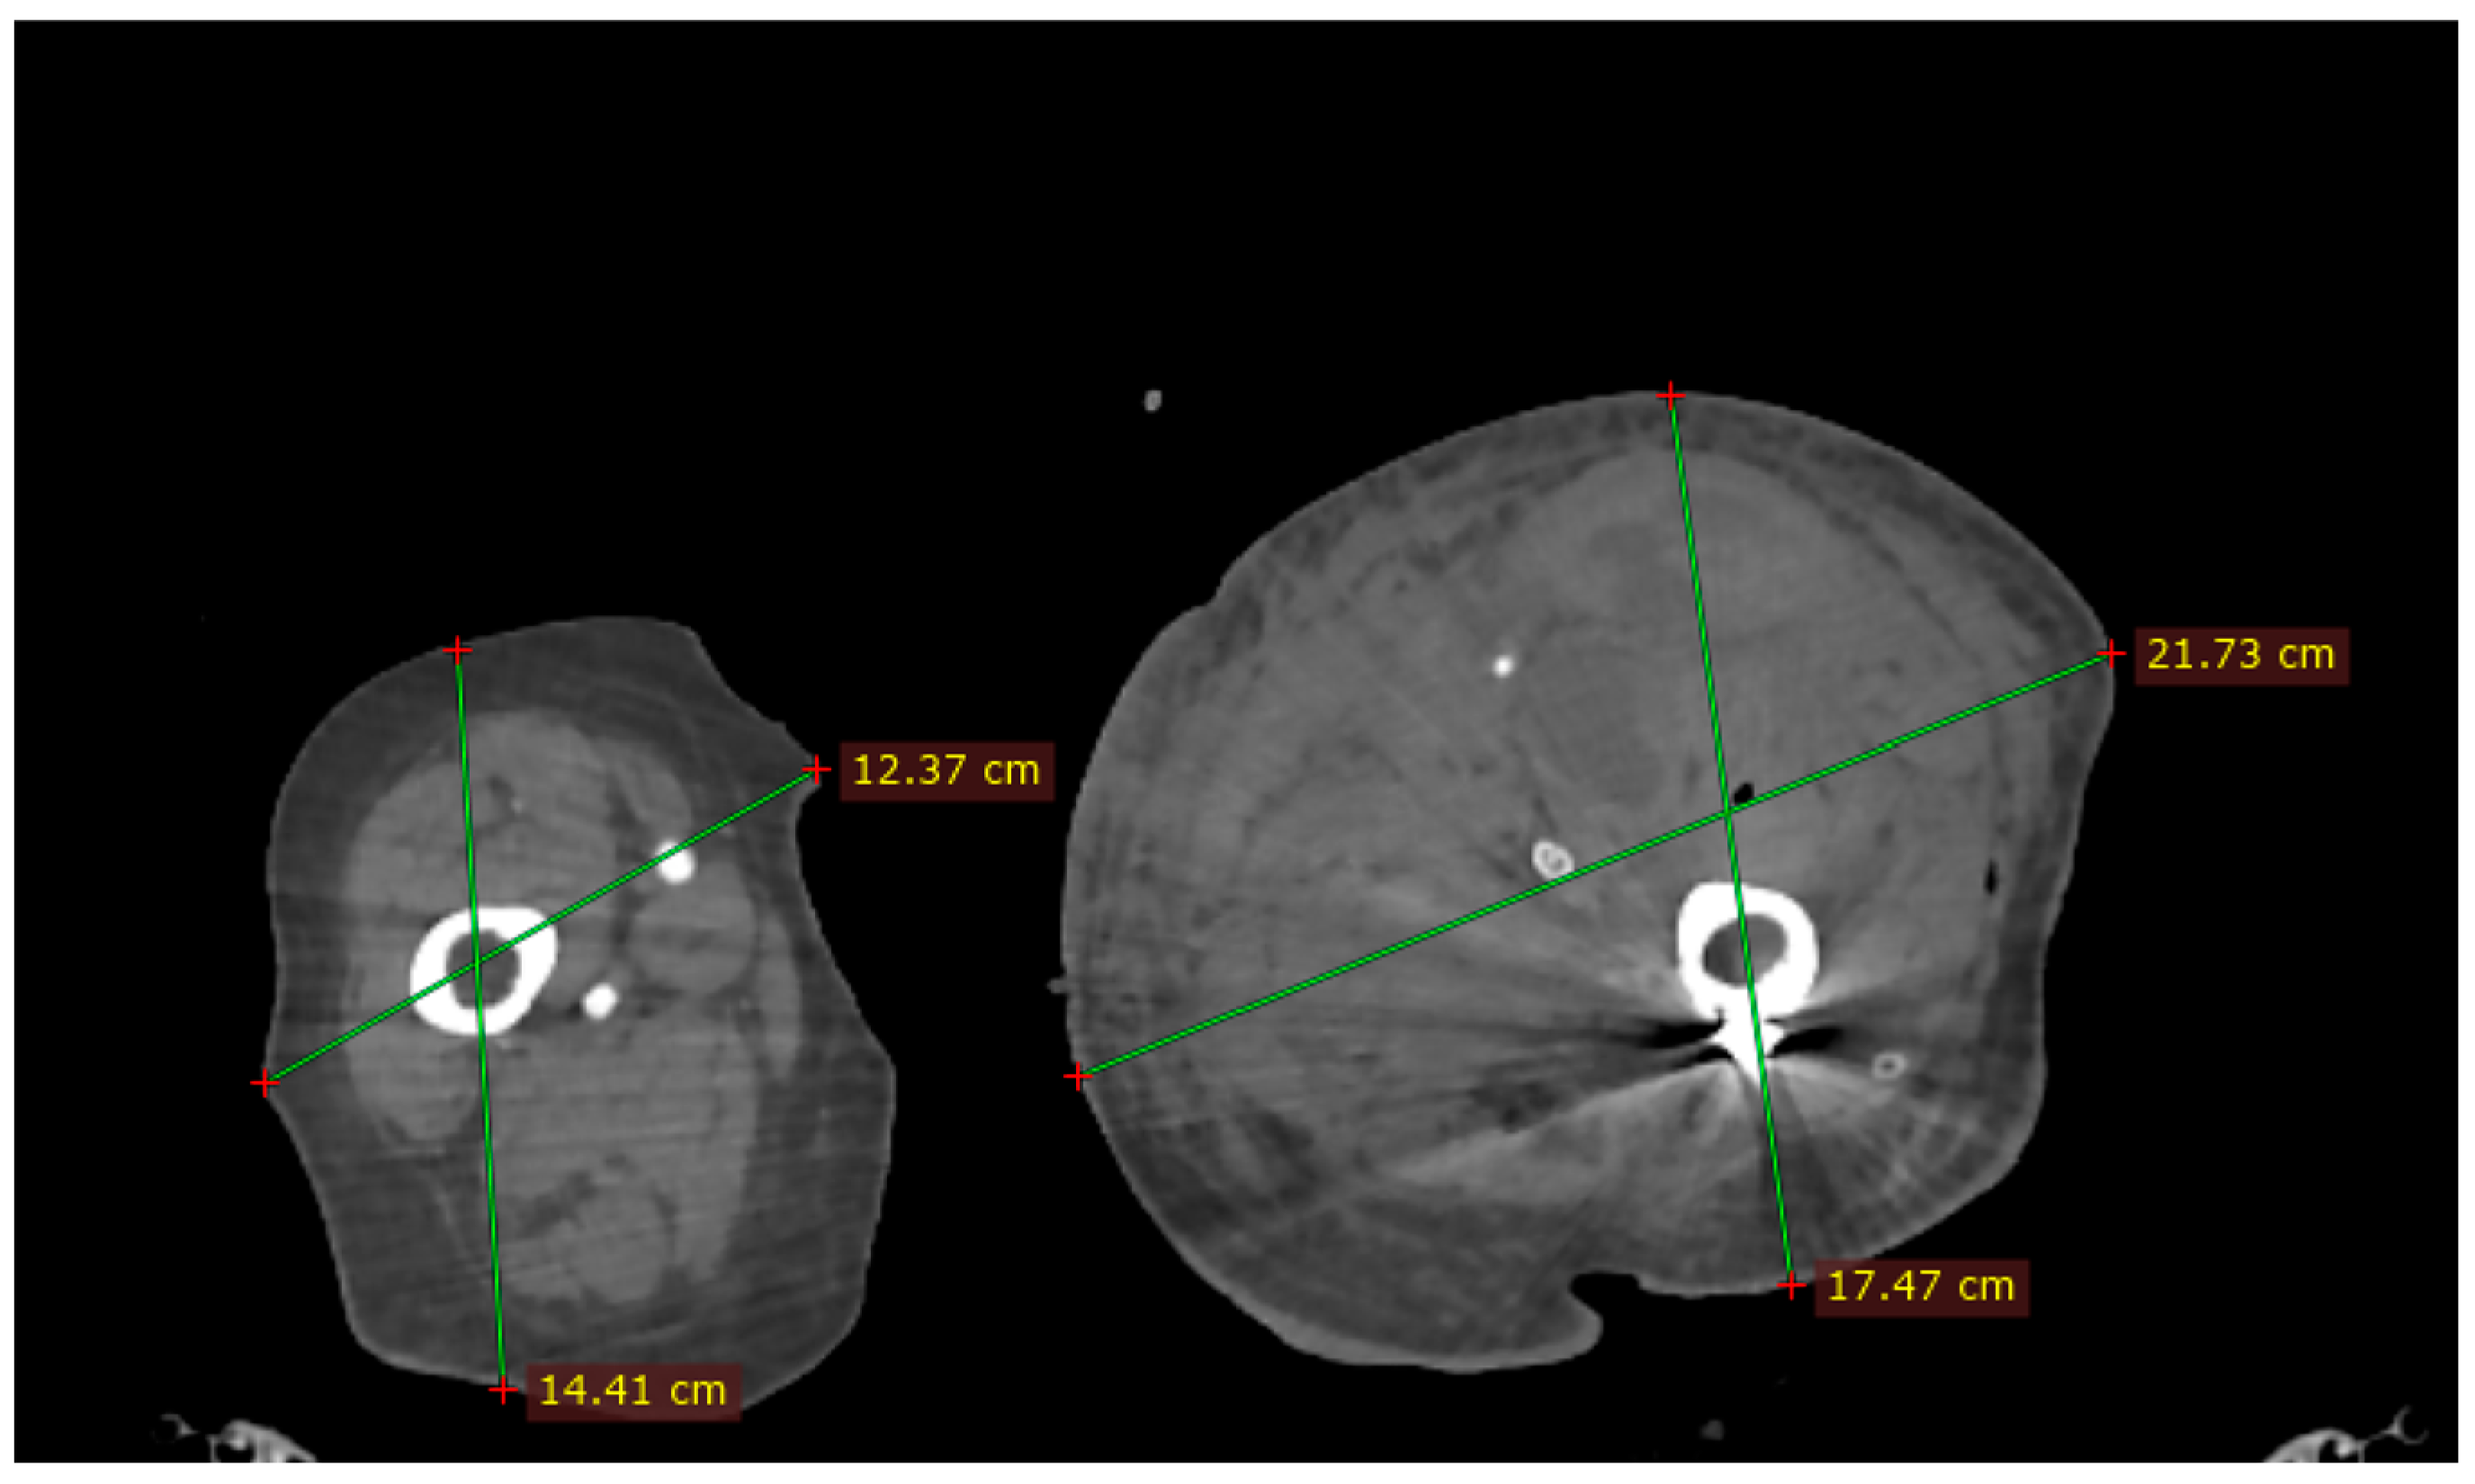

2. Case Presentation